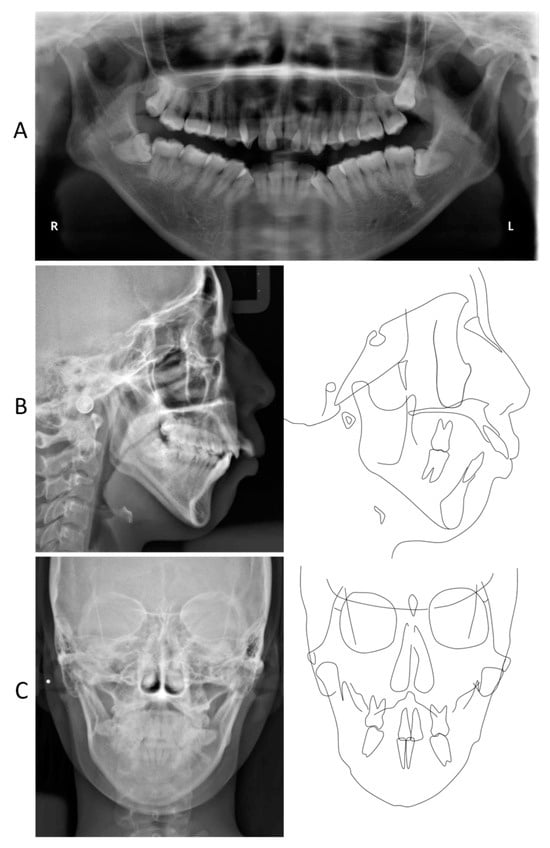

2. Detailed Case Description

| Japanese Adult Female | Pretreatment | Posttreatment | Postretention | ||

| Variables | Mean | SD | 25 y 0 m | 28 y 1 m | 32 y 6 m |

| Skeletal pattern | |||||

| SNA | 80.8 | 3.6 | 82.5 | 82.0 | 82.0 |

| SNB | 77.9 | 4.5 | 74.0 | 75.5 | 75.5 |

| ANB | 2.8 | 2.4 | 8.5 | 6.5 | 6.5 |

| Facial angle | 84.2 | 4.4 | 76.0 | 77.5 | 77.0 |

| Y-axis | 66.1 | 3.6 | 76.0 | 74.0 | 74.0 |

| Mand. pl./FH | 30.5 | 3.6 | 44.5 | 42.5 | 42.5 |

| Mand. pl./SN | 37.1 | 4.6 | 47.0 | 45.0 | 45.0 |

| Gonial angle | 122.1 | 5.3 | 135.0 | 134.5 | 134.5 |

| Denture pattern | |||||

| Occ. pl. to SN | 16.9 | 4.4 | 18.5 | 22.0 | 23.0 |

| U1 to SN | 105.9 | 8.8 | 121.0 | 91.5 | 91.5 |

| L1 to Mand. pl. | 93.4 | 6.8 | 86.5 | 95.5 | 95.0 |

| FMIA | 56.0 | 8.1 | 49.0 | 42.0 | 42.5 |

| Interincisal angle | 123.6 | 10.6 | 108.5 | 122.0 | 122.0 |